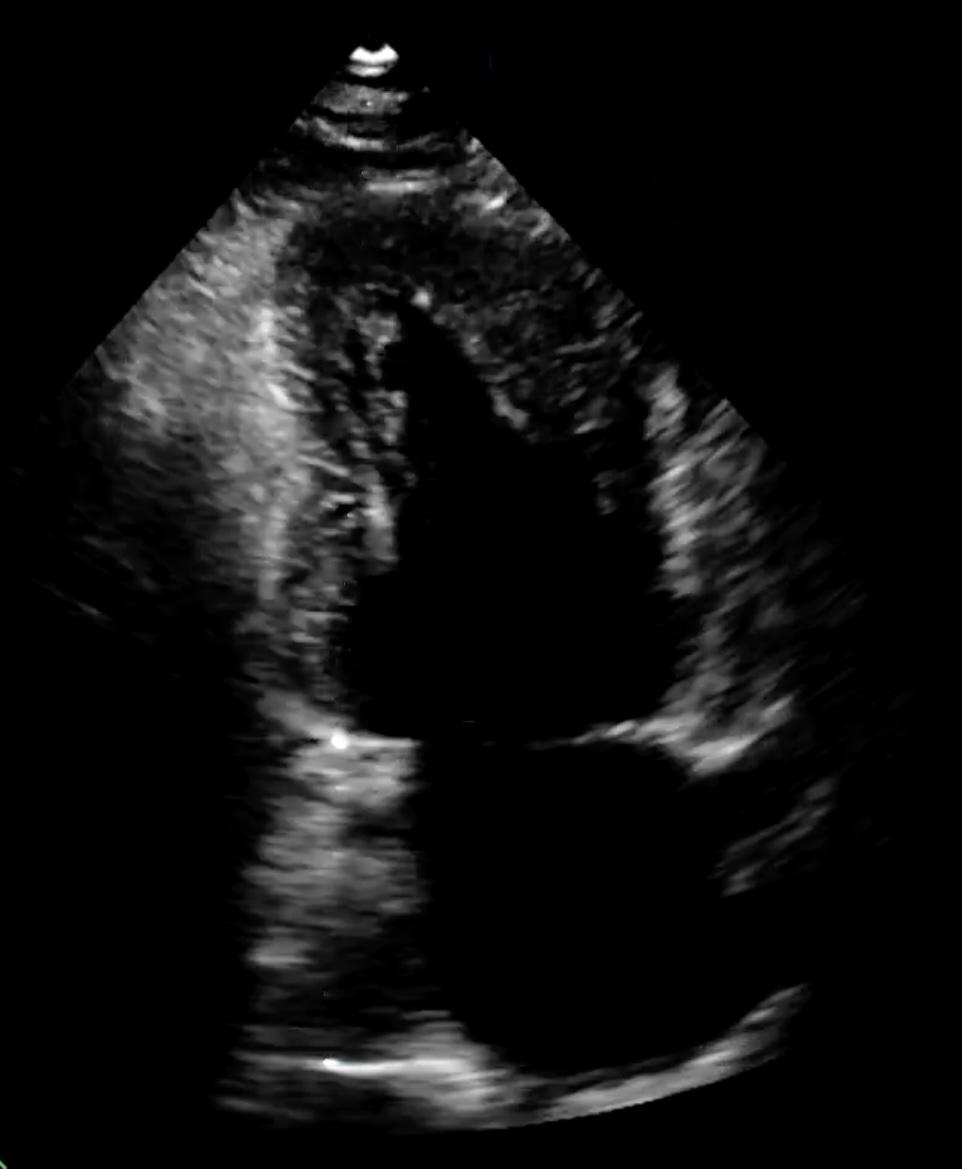

Bei einem 57-jährigen Patienten mit metastasiertem klarzelligem RCC zeigten sich in der CT-Verlaufskontrolle zwei neue, kontrastmittelanreichernde Läsionen im Myokard anteroapikal und septal, die differenzialdiagnostisch nicht sicher zwischen Thromben und Metastasen zu unterscheiden waren. Der Patient berichtete über Palpitationen, jedoch keine Dyspnoe oder Thoraxschmerzen. Das EKG ergab T-Wellen-Negativierungen in den Ableitungen V1–V6, NT-proBNP war mit 1670 pg/ml erhöht. Die transthorakale Echokardiographie zeigte eine fokale Wandverdickung anteroapikal und inferoseptal bei scharfer Abgrenzung des Endokards. Die linksventrikuläre Ejektionsfraktion lag bei etwa 55 %, Auffälligkeiten des rechten Ventrikels bestanden nicht. Zur differenzialdiagnostischen Abgrenzung erfolgte eine Kontrastechokardiographie, in der beide Läsionen eine deutliche Hypervaskularisation zeigten. Dieser Befund legte eine metastatische Genese nahe und war nicht mit dem avaskulären Erscheinungsbild thrombotischer Strukturen vereinbar. Aufgrund der Tumorprogression erfolgte ein Wechsel der systemischen Therapie von Sunitinib auf Belzutifan. Unter fortlaufender kardioonkologischer Betreuung ist der Patient derzeit klinisch stabil.

Myokardmetastasen eines RCC sind selten und werden häufig als Zufallsbefunde entdeckt. Die Abgrenzung zu intrakardialen Thromben stellt in der Bildgebung eine diagnostische Herausforderung dar. Mittels CT war in diesem Fall keine eindeutige Differenzierung möglich. Die Kontrastechokardiographie ermöglichte eine präzisere Beurteilung der Perfusion; das Tumorgewebe zeigte eine deutliche Hypervaskularisation, wodurch eine thrombotische Genese unwahrscheinlich war und auf eine ergänzende MRT verzichtet werden konnte.